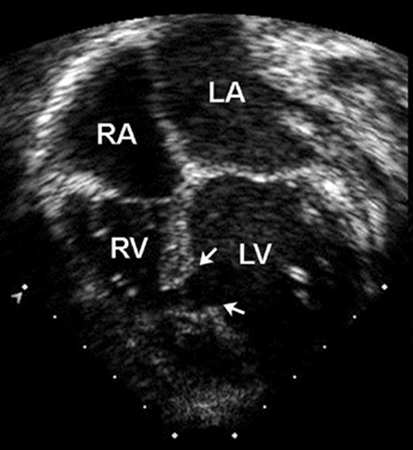

Imagem de ecocardiografia apical de 4 câmaras revelando dilatação do ventrículo direito em um paciente com defeito do septo atrial (DSA). (AD) átrio direito; (VD) ventrículo direito; (VE) ventrículo esquerdo

Imagem cedida por Patrick W. O'Leary, MD